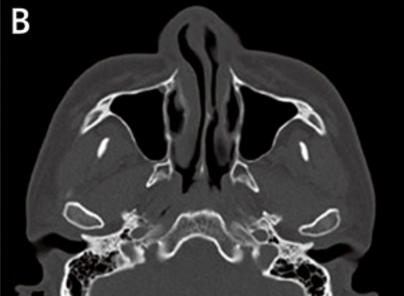

At VG Plastic Surgery, we carry out precise analysis and diagnosis procedures using 3D CT scans prior to surgery This is to analyze the problems that cannot be detected through consultation from a multi-faceted approach

An experienced plastic surgeon can determine the state of the nasal bone and the septal nasal cartilage based on a visual inspection alone. However, in order to determine the state of the nasal septum in the deeper parts, the degree of curvature of the nasal bone, the overall size and shape, and asymmetry, there is a need to perform a 3D analysis using 3D CT scans, which helps the surgeon formulate a more accurate and safer surgical plan. Of particular note, in the event of corrective nose surgery, a 3D analysis will reveal the state and notable characteristics of the implant and the septal nasal cartilage as well as the potential functional problems such as septal deviation in advance.

3D CT scans tailored to rhinoplasty procedures enable a multi-faceted analysis of the size and shape of the nasal bone, the septal nasal cartilage and the degree of curvature of the bone and/or cartilage and allow the surgeon to check for enlargement of the inferior nasal concha, presence of implants and determine the implant type and problems.